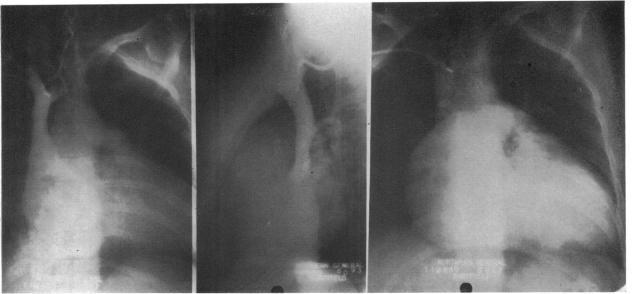

右三房心

Cor triatrium dexter.

A case of cor triatrium dexter is described in which the patient had been independently assessed in two cardiological centres as having a form of Ebstein's anomaly. The differential diognosis is discussed.

摘要

本文描述了一例右房三房心病例,该患者在两个心脏病中心分别独立评估为埃布斯坦畸形的一种类型。文中讨论了鉴别诊断。